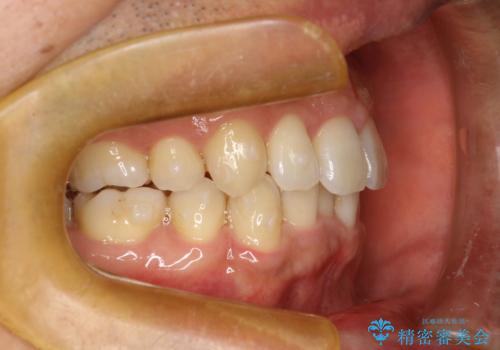

- 以前、上下左右4本抜いてワイヤー矯正をしていた方で、後戻りで下の前歯のガタガタを気にして来院されました。

マウスピース矯正にて、下の歯はIPR(歯と歯の間を削る)を入れることでガタガタの改善、咬み合わせの深さも改善をはかる治療計画をたてました。

歯と歯の間を削って隙間を作って矯正をしています。

保定装置(後戻り防止のための装置)は、基本的にはマウスピースタイプをお渡ししているのですが、患者様のご希望で取り外ししないタイプを希望されたので、前歯の裏側を細いワイヤーで固定(ボンディングリテーナー)を作成しています。